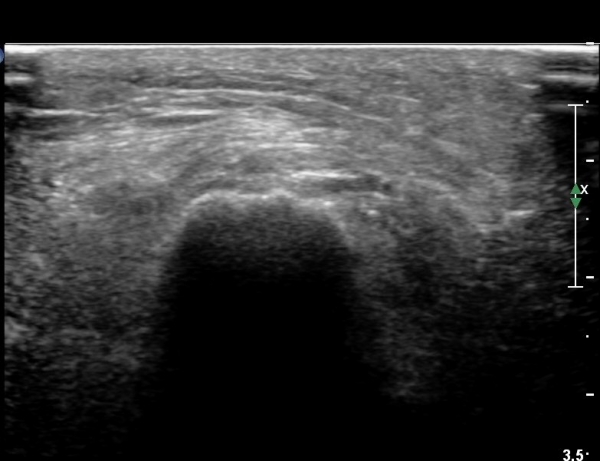

ŽÃËÀÚ¸¦ Á» ´õ ¸»´Ü, ¿ÜÃøÀ¸·Î À̵¿ÇÏ´Ï ºñ°ñµÎ Ç¥Ãþ¿¡¼­ ºñ°ñ½Å°æÀÌ Àú¿¡ÄÚ·Î °üÂûµÈ´Ù(»çÁø 3, 4, 5).